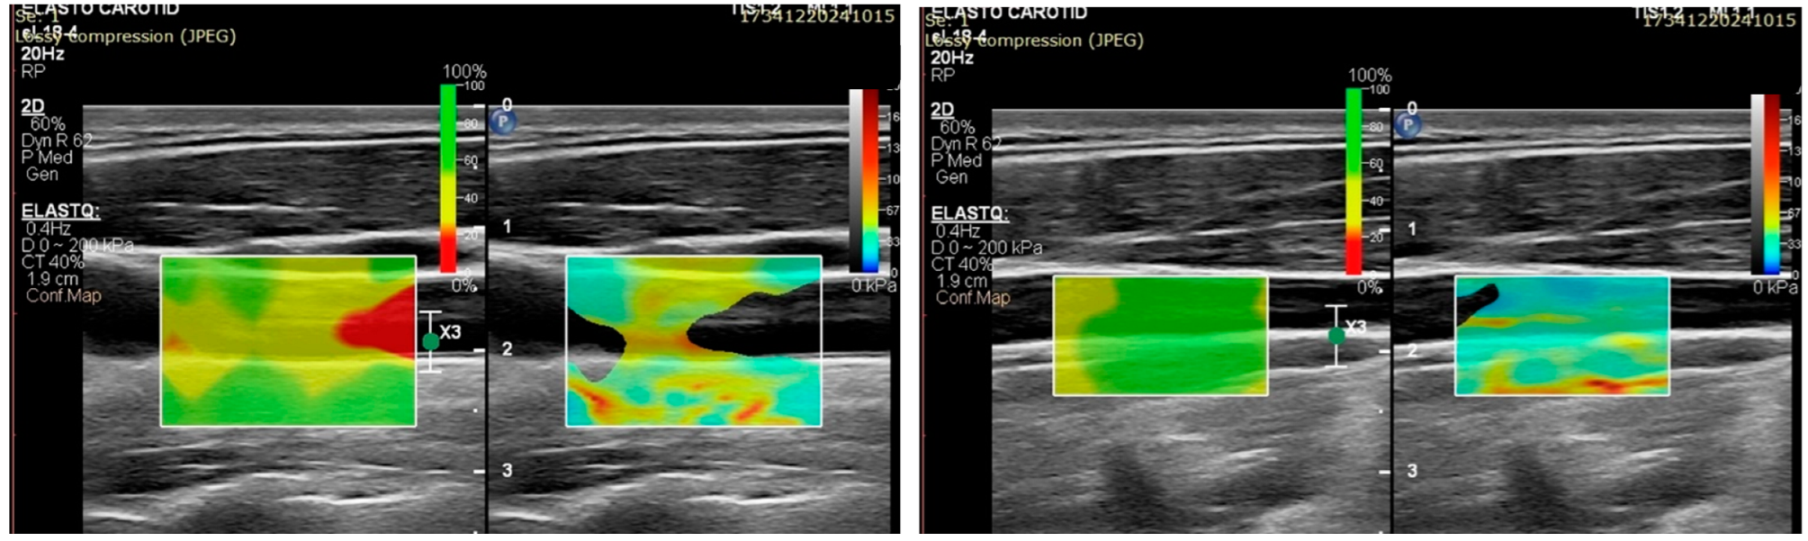

- A 2D color map of the shear wave velocities (SWVs) should be acquired, as it aids with the identification of homogeneous areas where the measurements are the most reliable. ROIs should be placed where the map shows a homogenous SWE distribution [56].

3.2. Assessing Carotid Plaques with Shear Wave Elastography